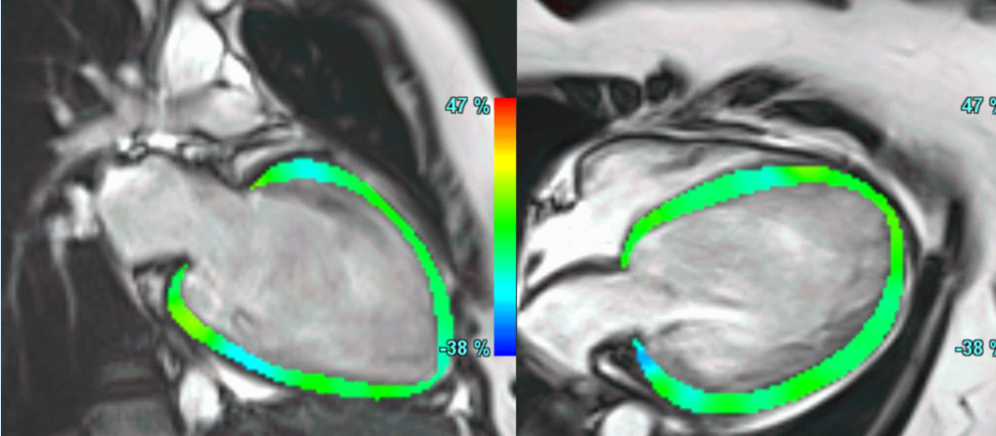

A common clinical presentation of LBBB induced cardiomyopathy is described in this post. It is always dilemma that if LBBB is cause or effect of dilated cardiomyopathy. However CMR can help in differentiating it from other causes and also in predicting response to device therapy. Utilise CMR to the fullest..!